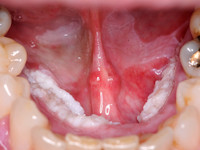

Orale floride papillomatose (oral florid papillomatosis) is een verruceus carcinoom van de mondholte. Het kan ook elders in de nasopharynx zitten. Het wordt ook wel een Ackerman tumor genoemd naar de patholoog Ackerman. De tumor gedraagt zich niet als een echt carcinoom. Het is een weinig agressief goed gedifferentieerd plaveiselcelcarcinoom. Sommigen beschouwen het als een soort overgangsstadium tussen een virale wrat en een verruceus carcinoom. Maar omdat ze erg groot kunnen worden veroorzaken ze wel klachten en schade. Het is een zeldzame aandoening, vooral voorkomend bij ouderen (> 60 jr), meer bij mannen dan bij vrouwen. De term orale papillomatose zonder de toevoeging floride wordt gebruikt voor gewone door HPV virus geïnduceerde wratten van de mondholte. Multipele orale papillomen worden ook gezien bij Heck disease (focale epitheliale hyperplasie).

Histologisch gaat het om goed gedifferentieerde plaveiselcelcarcinomen met een verruceuze architectuur. De tumoren groeien langzaam, zijn wel lokaal invasief en verdringend, metastaseren zelden. Er worden twee belangrijke oorzaken genoemd: HPV infectie (humaan papilloma virus) en roken, en nog vaker het pruimen (kauwen) van tabak wat in grote delen van de wereld nog gedaan wordt.